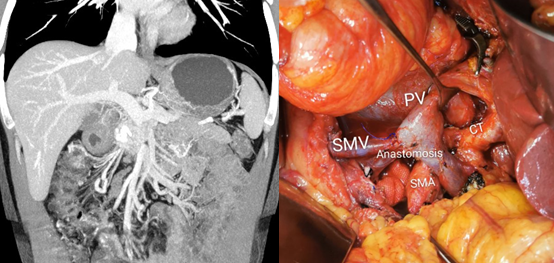

联合脏器或血管切除的扩大根治术

虽然胰腺神经内分泌肿瘤侵袭性弱于胰腺癌,但由于该类肿瘤常无临床症状,发现时往往肿瘤体积较大,所以肿瘤侵犯周围脏器或者重要血管的情况并不少见。联合血管切除在胰腺癌治疗中已经被广泛认可,同样在胰腺神经内分泌肿瘤上也适用(图5)。

图5 患者诊断为胰头部NET侵犯肠系膜上静脉,CAPTEM方案新辅助化疗后行根治性胰十二指肠切除+肠系膜上静脉重建+扩大腹腔淋巴结清扫。